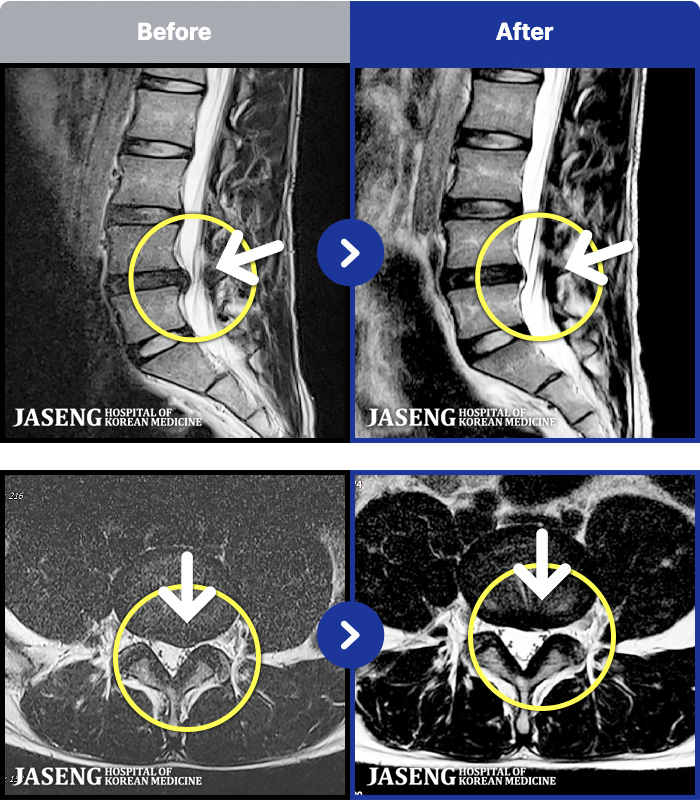

1,268 MRI ũ ʸ Ȯϼ.